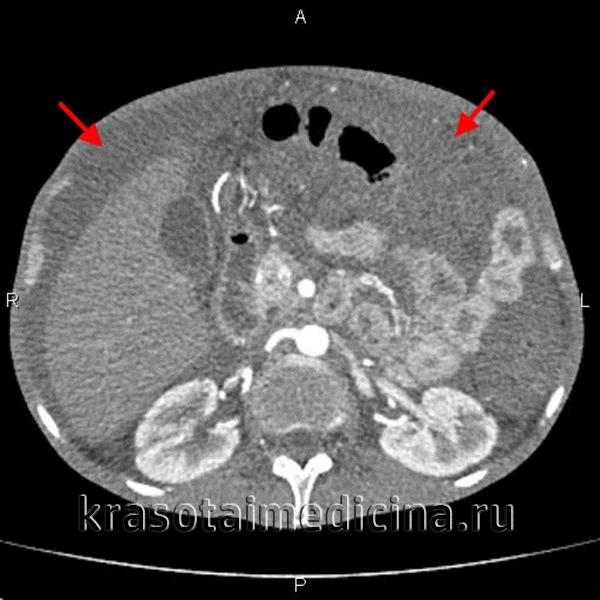

Асцит (от греческого «askos» — сумка, мешок) — это состояние, при котором наблюдается патологическое накопление жидкости в брюшной полости. Фоном для развития асцита в 81,5% случаев являются заболевания печени (цирроз печени, острый алкогольный гепатит, цирроз-рак), в 10% — злокачественные опухоли, в 3% — застойная сердечная недостаточность, в 1,7% — туберкулезный перитонит.

Скопление жидкости в брюшной полости является самой частой, но не единственной причиной увеличения размера живота и растяжения его стенки. Также необходимо исключить беременность, растяжение кишечника газами, кисты (яичника, брыжейки, ретроперитонеальные), растяжение полых органов — желудка, мочевого пузыря и ожирение. Асцит в зависимости от количества асцитической жидкости подразделяют на минимальный (выявляется только при инструментальном ультразвуковом исследовании и компьютерной томографии брюшной полости), умеренный (легко выявляется при физикальном исследовании) и выраженный (при значительном увеличении размера живота).